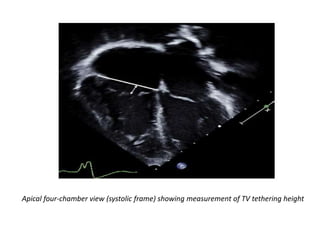

• Measurements of the TV tethering height and area have been

shown in adult patients with functional TR and with pulmonary

hypertension to provide insights into the mechanism of

regurgitation.

Apical four-chamber view (systolic frame) showing measurement of TV tethering height

• It is important to note that with TV annular dilatation, the